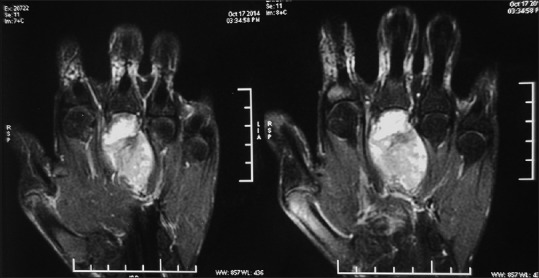

A 24-year-old male presented at a different center with a 1½-year history of gradually increasing swelling over dorsum of the left hand. He had no personal or family history of NF-1. X-ray of the left hand showed a lytic expansile lesion at the base of the third metacarpal bone. Contrast-enhanced magnetic resonance imaging (MRI) of the left hand revealed a 6.7 cm × 3.4 cm × 3.0 cm expansile destructive lesion involving the entire third metacarpal bone. The proximal and distal articular surfaces were free [Figure 1]. Biopsy showed pleomorphic round cell tumor with the possibility of Ewing's sarcoma in view of focal positivity of CD-99. Metastatic workup in the form of computerized tomography scan of chest, whole body bone scan, and bone marrow aspirate and biopsy was essentially normal.

| Figure 1:Contrast-enhanced magnetic resonance imaging of the left hand showing a diffusely enhancing 6.7 cm × 3.4 cm × 3.0 cm expansile destructive lesion involving the entire third metacarpal bone sparing the proximal and distal articular surfaces